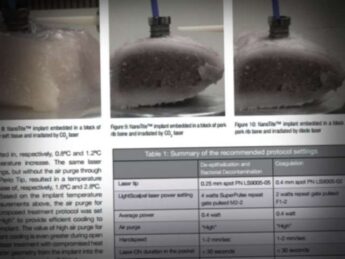

Surgical Laser Equipment: A flexible fiber dental CO2 laser LightScalpel LS-1005 was utilized with a dental angled tipless handpiece with a 0.25-mm focal spot diameter.

Laser Settings: 3 watts; SuperPulse Repeat Pulse Mode F1-6